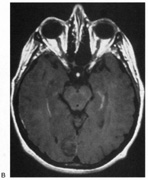

Fig. 10. Striate quadrantanopia. A. A 68-year-old woman with a stroke 3 years previously, causing left inferior quadrantanopia. B. MRI shows infarct of the superior bank of the right calcarine cortex.

Selective lesions can also occur along the anterior-posterior extent of striate cortex. A lesion of the occipital pole alone causes homonymous central hemiscotomata (Fig. 11).44,50 This can occur with watershed infarcts during systemic hypoperfusion. Slightly more anterior lesions in the middle zone of striate cortex cause homonymous peripheral scotomata (Fig. 12). The highly congruent, homonymous nature of these defects and their restriction to one hemifield differentiate these from ocular causes of central or paracentral visual loss. Lesions with such small field defects can be missed on CT.43 MRI with coronal sections through the occipital lobes should be performed, although even this may miss small lesions, particularly at the occipital pole.